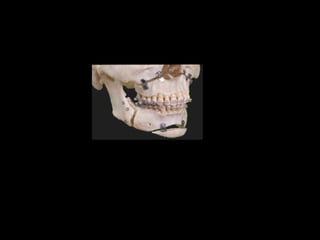

Fractura

Impacción de muñón

En cavida glenoidea

Pseudoclase II

Contractura traumática de

Músculo masetero y

Pterigoideos

Fractura Impacción de muñón Encavida glenoidea Pseudoclase II Contractura traumática de Músculo masetero y Pterigoideos